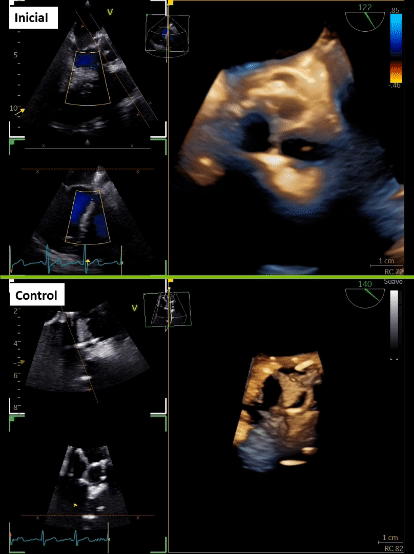

Tras 3 meses de cirugía cardiaca, consulta en urgencia por historia de 2 semanas de evolución caracterizada por dolor abdominal en flanco derecho que se irradia a región lumbar, acompañado de escalofríos de predominio vespertinos, y en exámenes destacan parámetros inflamatorios elevados. Inicialmente se realizó estudio imagenológico abdominal que sugirió pielonefritis aguda derecha, no obstante, destacó orina completa normal y urocultivo negativo. Se trasladó a medicina interna, donde se realizan hemocultivos que resultaron positivos a Stafilococcus warneri. Dado microorganismo, se realiza estudio con sospecha de endocarditis, con un primer estudio ecocardiográfico transtorácico y transesofágico que fue informado como negativo para endocarditis. Tras 7 días aproximadamente, con una alta sospecha, se complementan hallazgos con nuevo ecocardiograma transesofágico que describe velo protésico izquierdo tapizado de vegetaciones (Figura 1A, 1B y 1C; Video 1), pero dada cirugía cardiaca reciente los hallazgos a nivel de la fibrosa mitro-aórtica no fueron categóricos. Se realiza tomografía con emisión de positrones (PET)/CT con 18 F-flurodesoxiglucosa (F-FDG) que informó válvula aórtica protésica con tejido hipermetabólico de partes blandas en relación a válvula protésica, de aspecto inflamatorio. Además, en paralelo se solicita TCC que informa lesión nodular de la prótesis aórtica en relación a velo coronario izquierda de 16 x 8 mm, asociado a cambios inflamatorios que rodean al origen de la arteria coronaria izquierda que se extienden a la fibrosa mitro-aórtica con laguna que nace en el tracto de salida inmediatamente subvalvular, y otra laguna vascular adyacente al marco de la prótesis compatible con pseudoaneurisma (Figura 1D y 1E).

Con los hallazgos descritos, se realiza resolución quirúrgica, donde se evidencia absceso anular y velo protésico izquierdo comprometido con endocarditis (figura 1F, 1G y 1H). Luego, se realiza recambio valvular aórtico biológico, con evolución post-operatoria sin complicaciones quirúrgicas y sucesivamente el paciente fue dado de alta tras completar terapia antibiótica con buena evolución clínica.